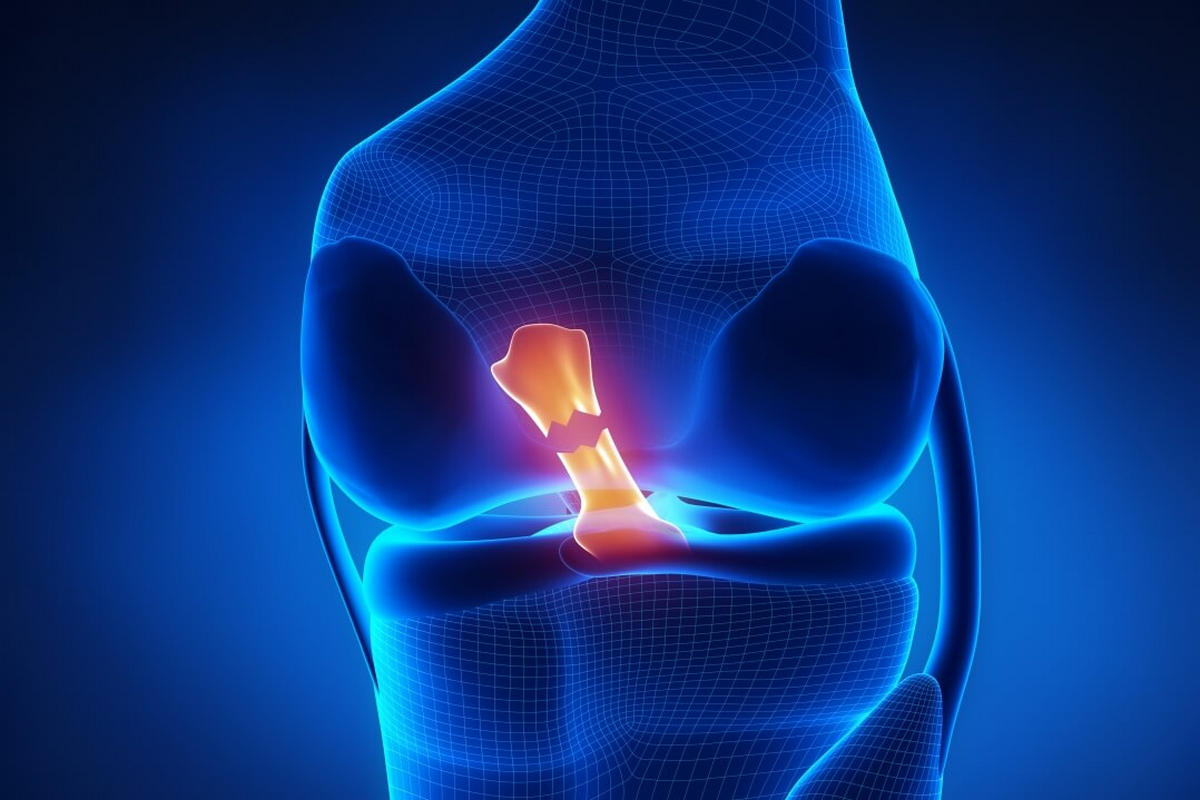

Ο πρόσθιος χιαστός σύνδεσμος βρίσκεται στο εσωτερικό της άρθρωσης του γόνατος και αποτελεί βασικό σταθεροποιητικό μηχανισμό. Ελέγχει:

Την πρόσθια μετατόπιση της κνήμης σε σχέση με το μηρό

Τις στροφικές κινήσεις του γόνατος

Όταν προκληθεί ρήξη πρόσθιου χιαστού, το γόνατο χάνει τη φυσιολογική του σταθερότητα, δημιουργώντας αίσθημα αστάθειας και «φεύγει το γόνατο» κατά τη φόρτιση ή την άθληση.